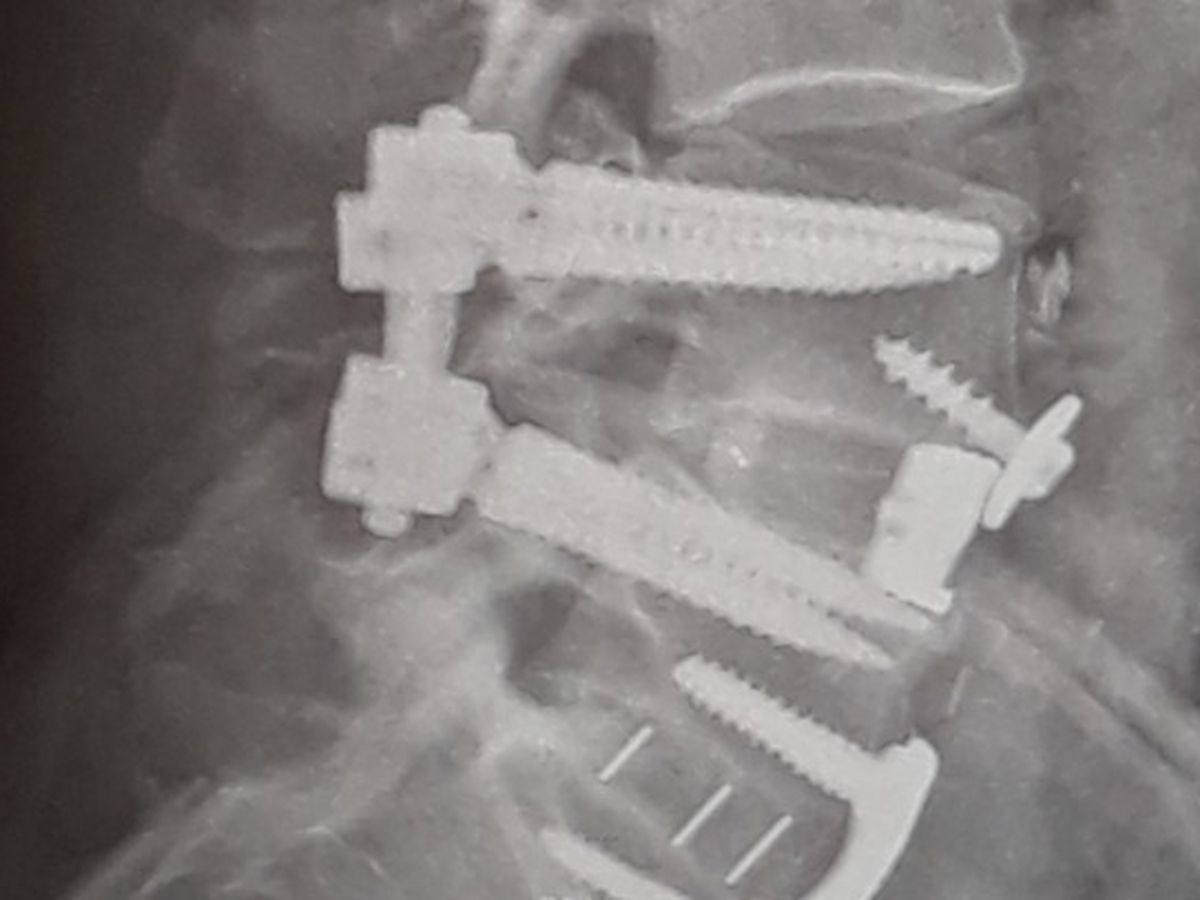

Nerves in my spine were damaged during back surgery causing pain down legs into feet, numbing feet, and chronic lower back pain with constant spasms.